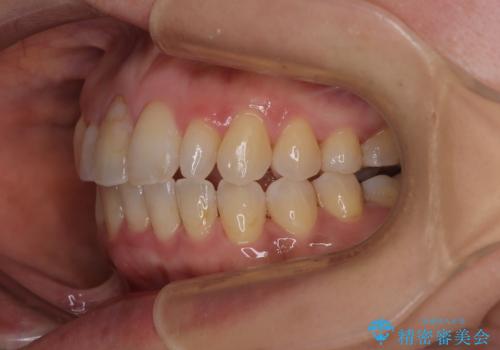

骨格的なズレを歯列矯正でカバー ワイヤー装置での非抜歯矯正

- 前歯のデコボコと咬み合わせの悪さを気にして来院された患者様です。

下顎骨が左側にズレて成長してしまったため、左側の咬み合わせが上下反対になっている状態でした。

骨格的なズレは歯列矯正のみでは改善できず、骨切除が必要となります。

そこまでの処置は望んでいらっしゃらなかったため、歯列矯正でのカムフラージュにより咬み合わせを改善することとしました。

予想通り左側の咬み合わせの調整に苦労をしましたが、最終的には違和感のない咬み合わせを達成することができました。